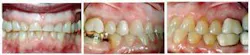

A 55-year-old female presented for restorative treatment of her anterior teeth (Figure 1). She had a history of bulimia during college, which resulted in extensive erosion of her maxillary anterior teeth. Her lower anterior teeth had super-erupted, leaving her with a reverse smile line. Upon clinical examination, we noted that she had good oral hygiene, extensive incisal tooth loss of all her anterior teeth, erosion at the cementoenamel junction, and a history of clenching/grinding. She reported that she had controlled the bulimia for years, and was seeking good esthetics and function.